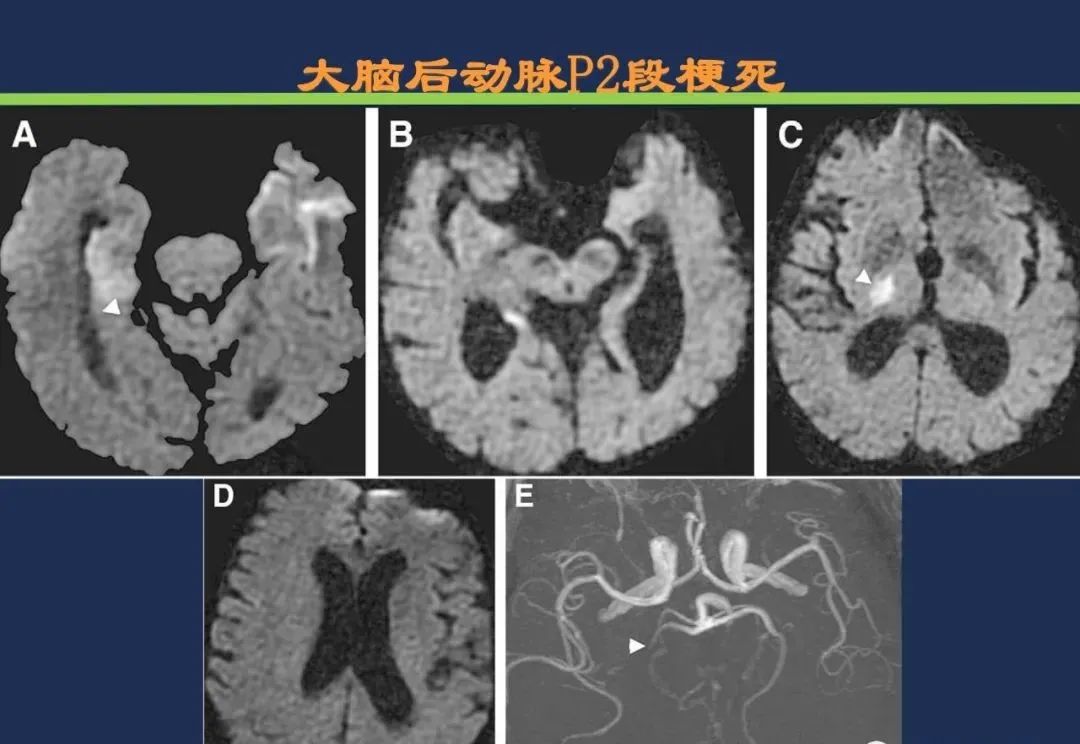

椎基底动脉梗死大脑后动脉丘脑穿通动脉-Percheron动脉